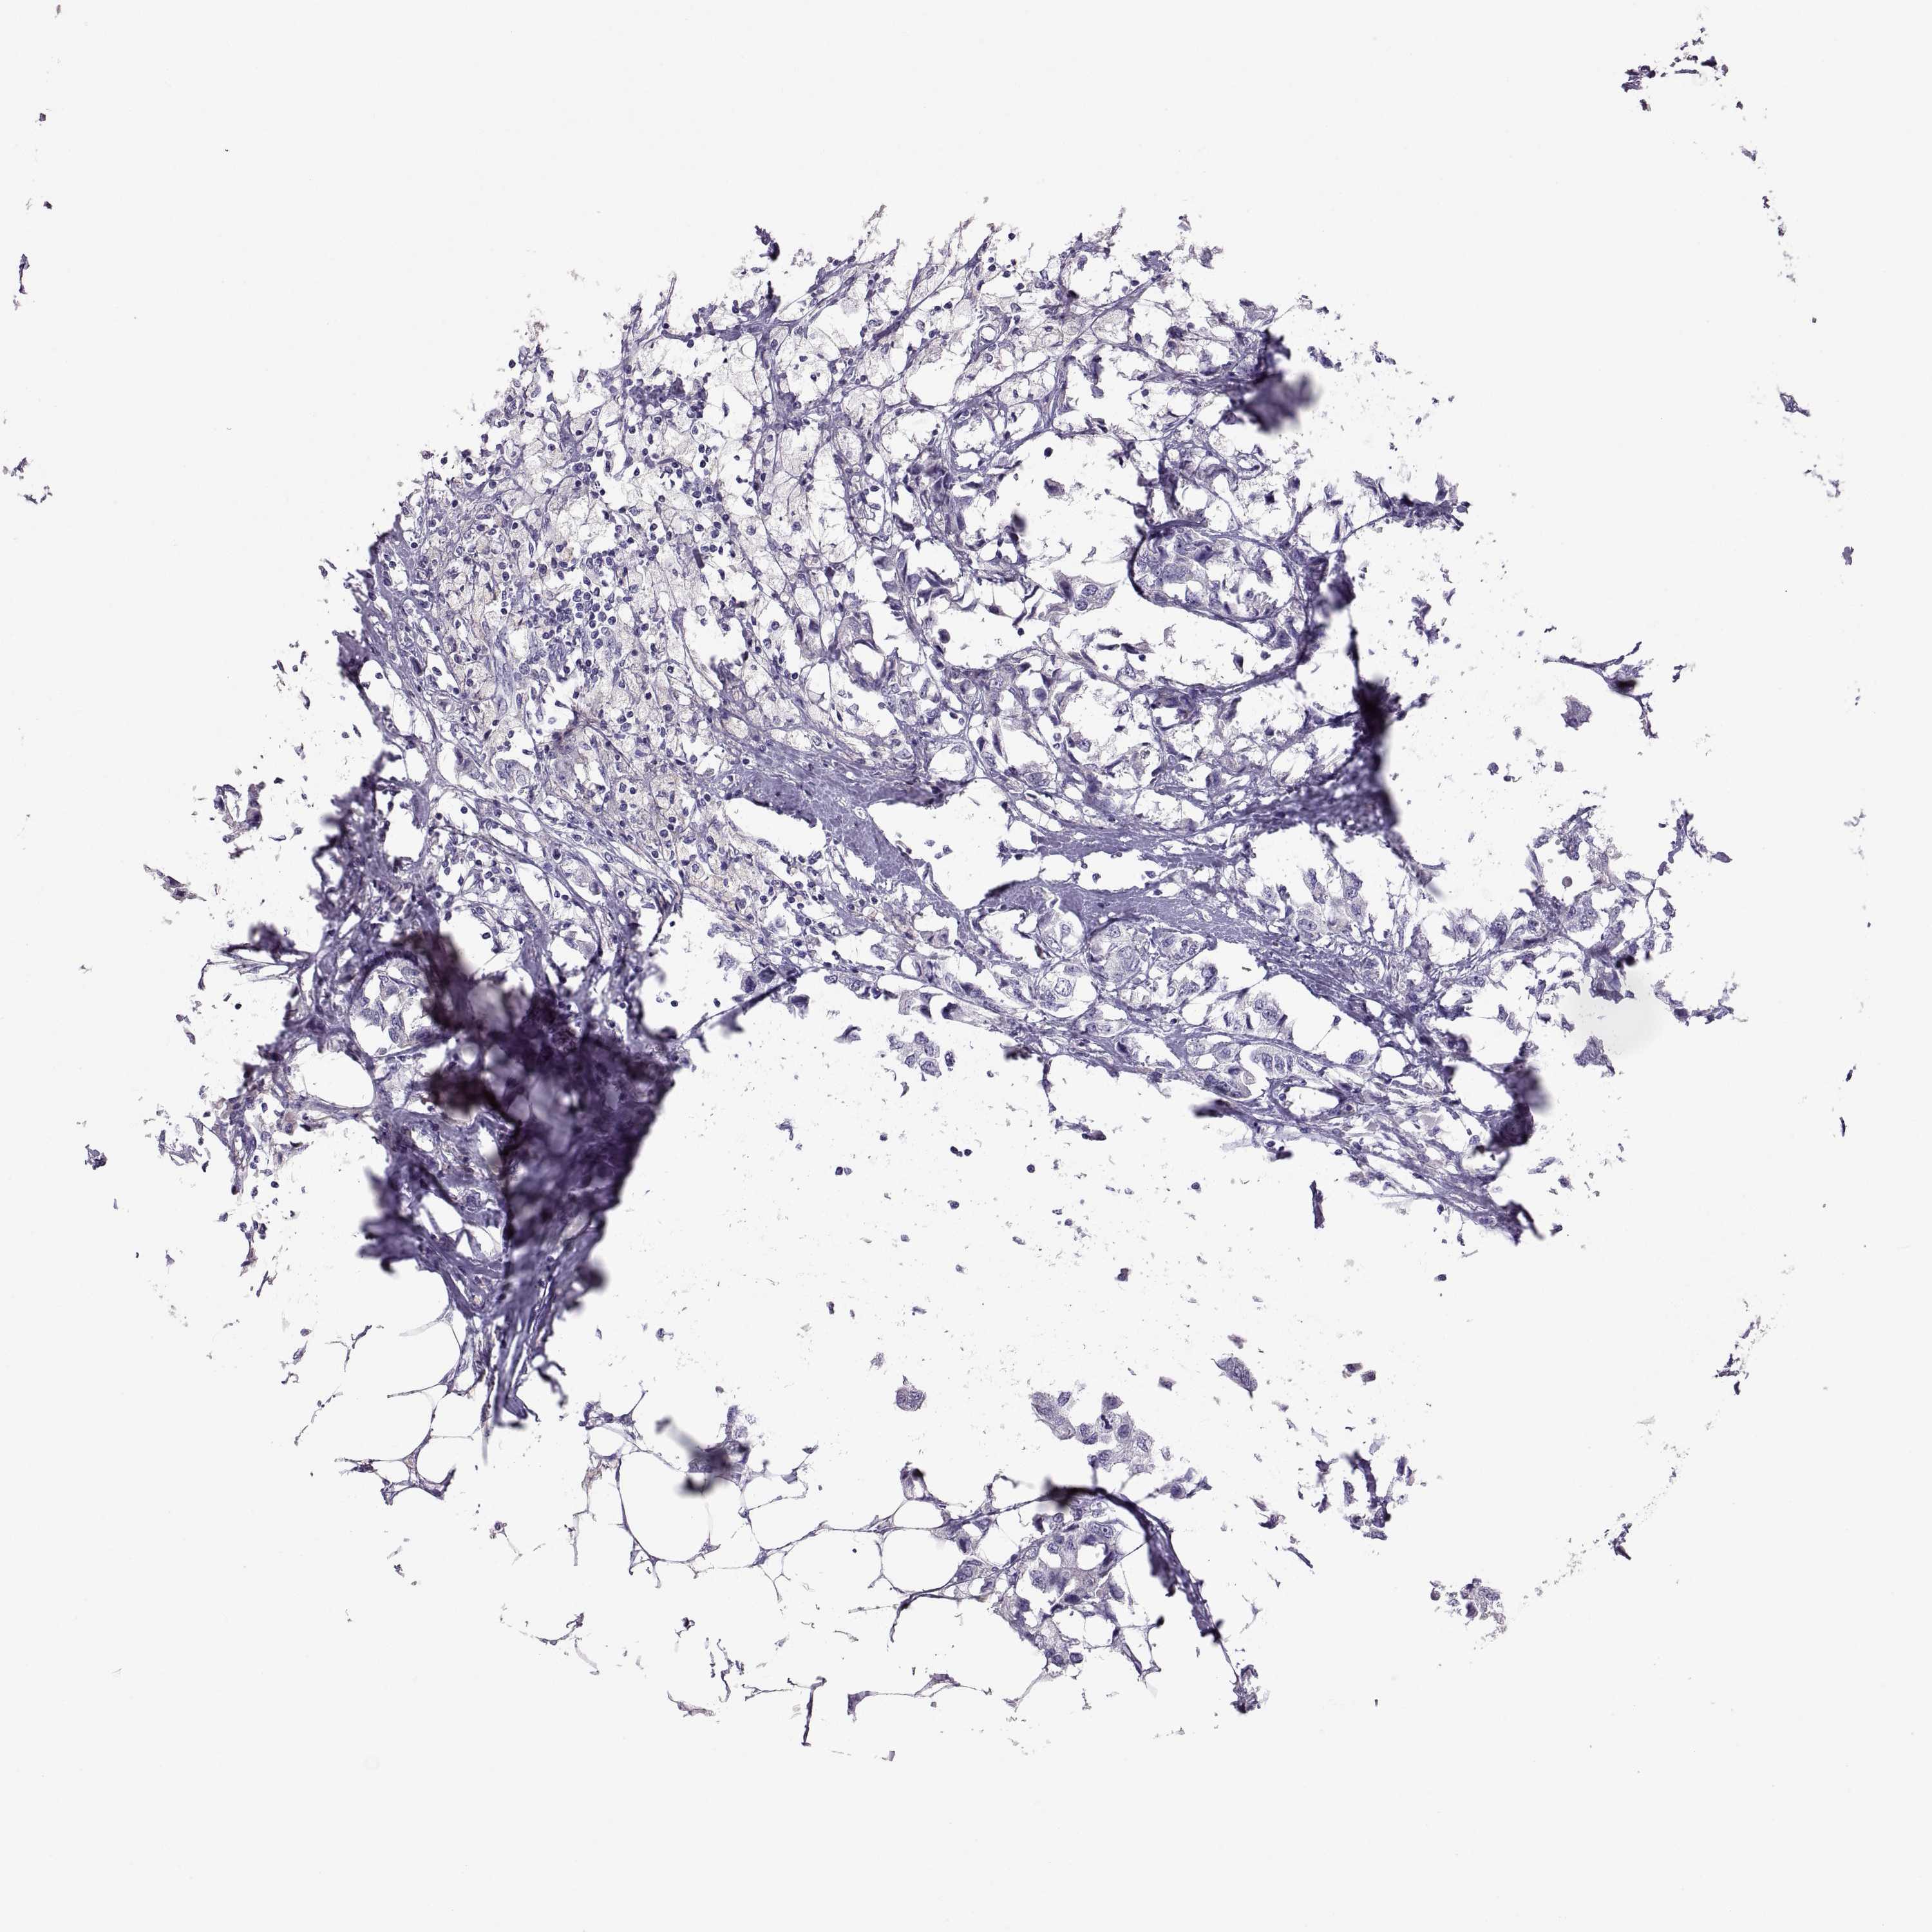

BRCA TCGA BRCA VALIDATION PROTEIN EXPRESSION

Breast cancer

Human cancer